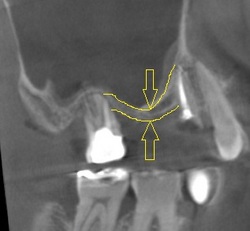

患者さんで、「骨がなくてインプラントはできない」と他院で言われた患者さんが来院されました。

丸で囲まれた部位は、上のあごの骨のCT画像です。

黄色の矢印の幅しか骨がなく他院ではインプラントはできないと言われたそうです。

当院では、インプラントの専門医がいるため、ソケットリフトという特殊な方法を用いてインプラント治療を行いました。

処置後は、痛み腫れは無く、患者さんは大変満足していました。

このほかにも他院でインプラントができないと言われた患者さんにインプラント治療を行い、喜んでいただいた症例がたくさんあります。

他院でインプラントができないと言われた患者さんは是非ご相談ください。